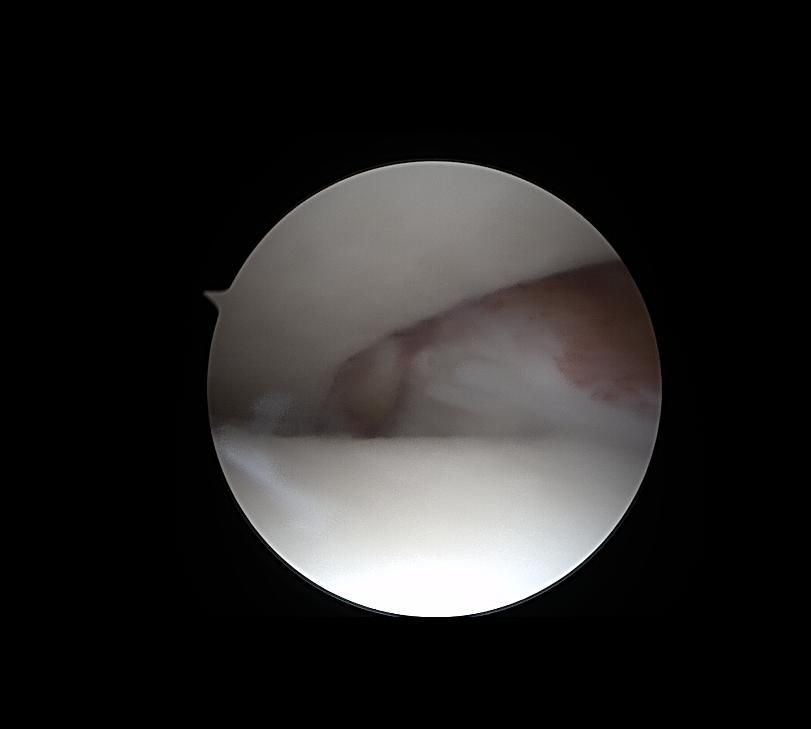

제가 발목 연골손상이라 mri와 내시경 사진이 있는데

어떤 상태인지 좀 다른 고견을 들어보고자 합니다

• 4번 째 사진

발목 연골의 손상 같은 경우 손상 정도에 따라 회복 가능성 및 회복 기간의 차이가 있을 수 있으며 완전 손상 같은 경우 수술이 필요할 수 있지만 부분적인 손상 같은 경우 수술 없이 보존적인 치료가 가능하며 주사나 약물치료 재활치료 등을 통해 회복이 가능합니다.

연골 손상이 발생하여도 전문적인 치료와 적절한 재활 및 꾸준한 관리를 통해 충분히 회복을 하실 수 있고, 일상생활 및 보행에 큰 지장이 발생하지 않을 것으로 생각합니다.